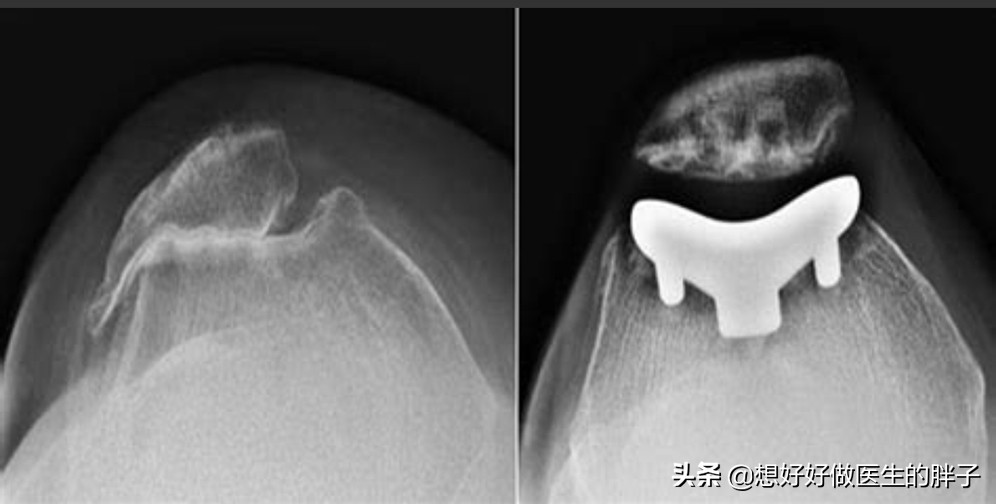

●当软骨磨损特别严重,患者疼痛比较明显的时候,就没有必要浪费金钱进行核磁检查了,因为此时因为软骨磨损的特别严重,髌骨以及后方的股骨关节间隙已经出现了明显的狭窄,而且形态已经发生了明显的改变,做普通x线检查就可以明确问题了。

●当软骨磨损特别严重以后,关节间隙会有明显的狭窄,患者关节功能将会明显的受限,而且会伴有难以忍受的疼痛,此时可能需要进行髌骨股骨关节置换,才能彻底的帮助患者解决问题了。